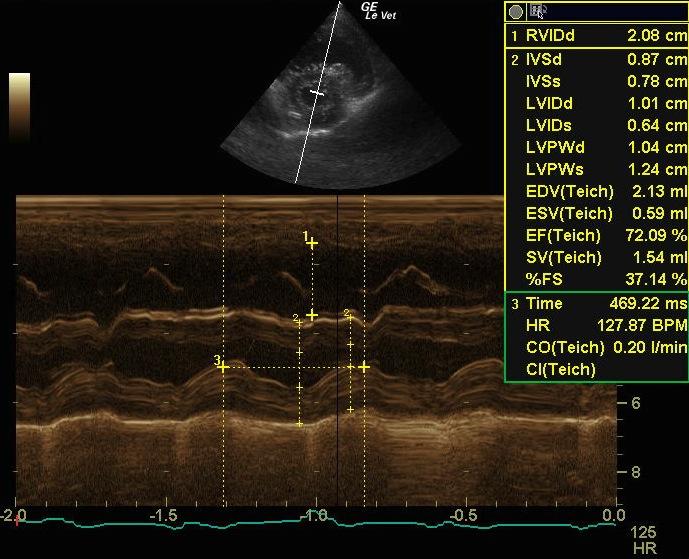

The left ventricular cavity is small in diastole (1.6 cm) and systole (1.0 cm) with a normal fractional shortening (37 %). There is flattening of the interventricular septum in systole, consistent with right ventricular hypertension. The left ventricular walls are relatively hypertrophied (0.65 cm septal wall and 0.65 cm free wall). The right ventricle appears markedly hypertrophied, and the right atrium appears moderately enlarged in size. The main pulmonary artery appears significantly enlarged in comparison to the aorta. There is moderate tricuspid regurgitation on Doppler exam with the jet directed toward the aorta. The velocity is also markedly increased to 4.73 m/sec, describing a pressure gradient of 90 mmHg, consistent with pulmonary hypertension. The heart rate is measured at 124 to 149 BPM and a regular sinus rhythm is seen on an ECG run during the exam.